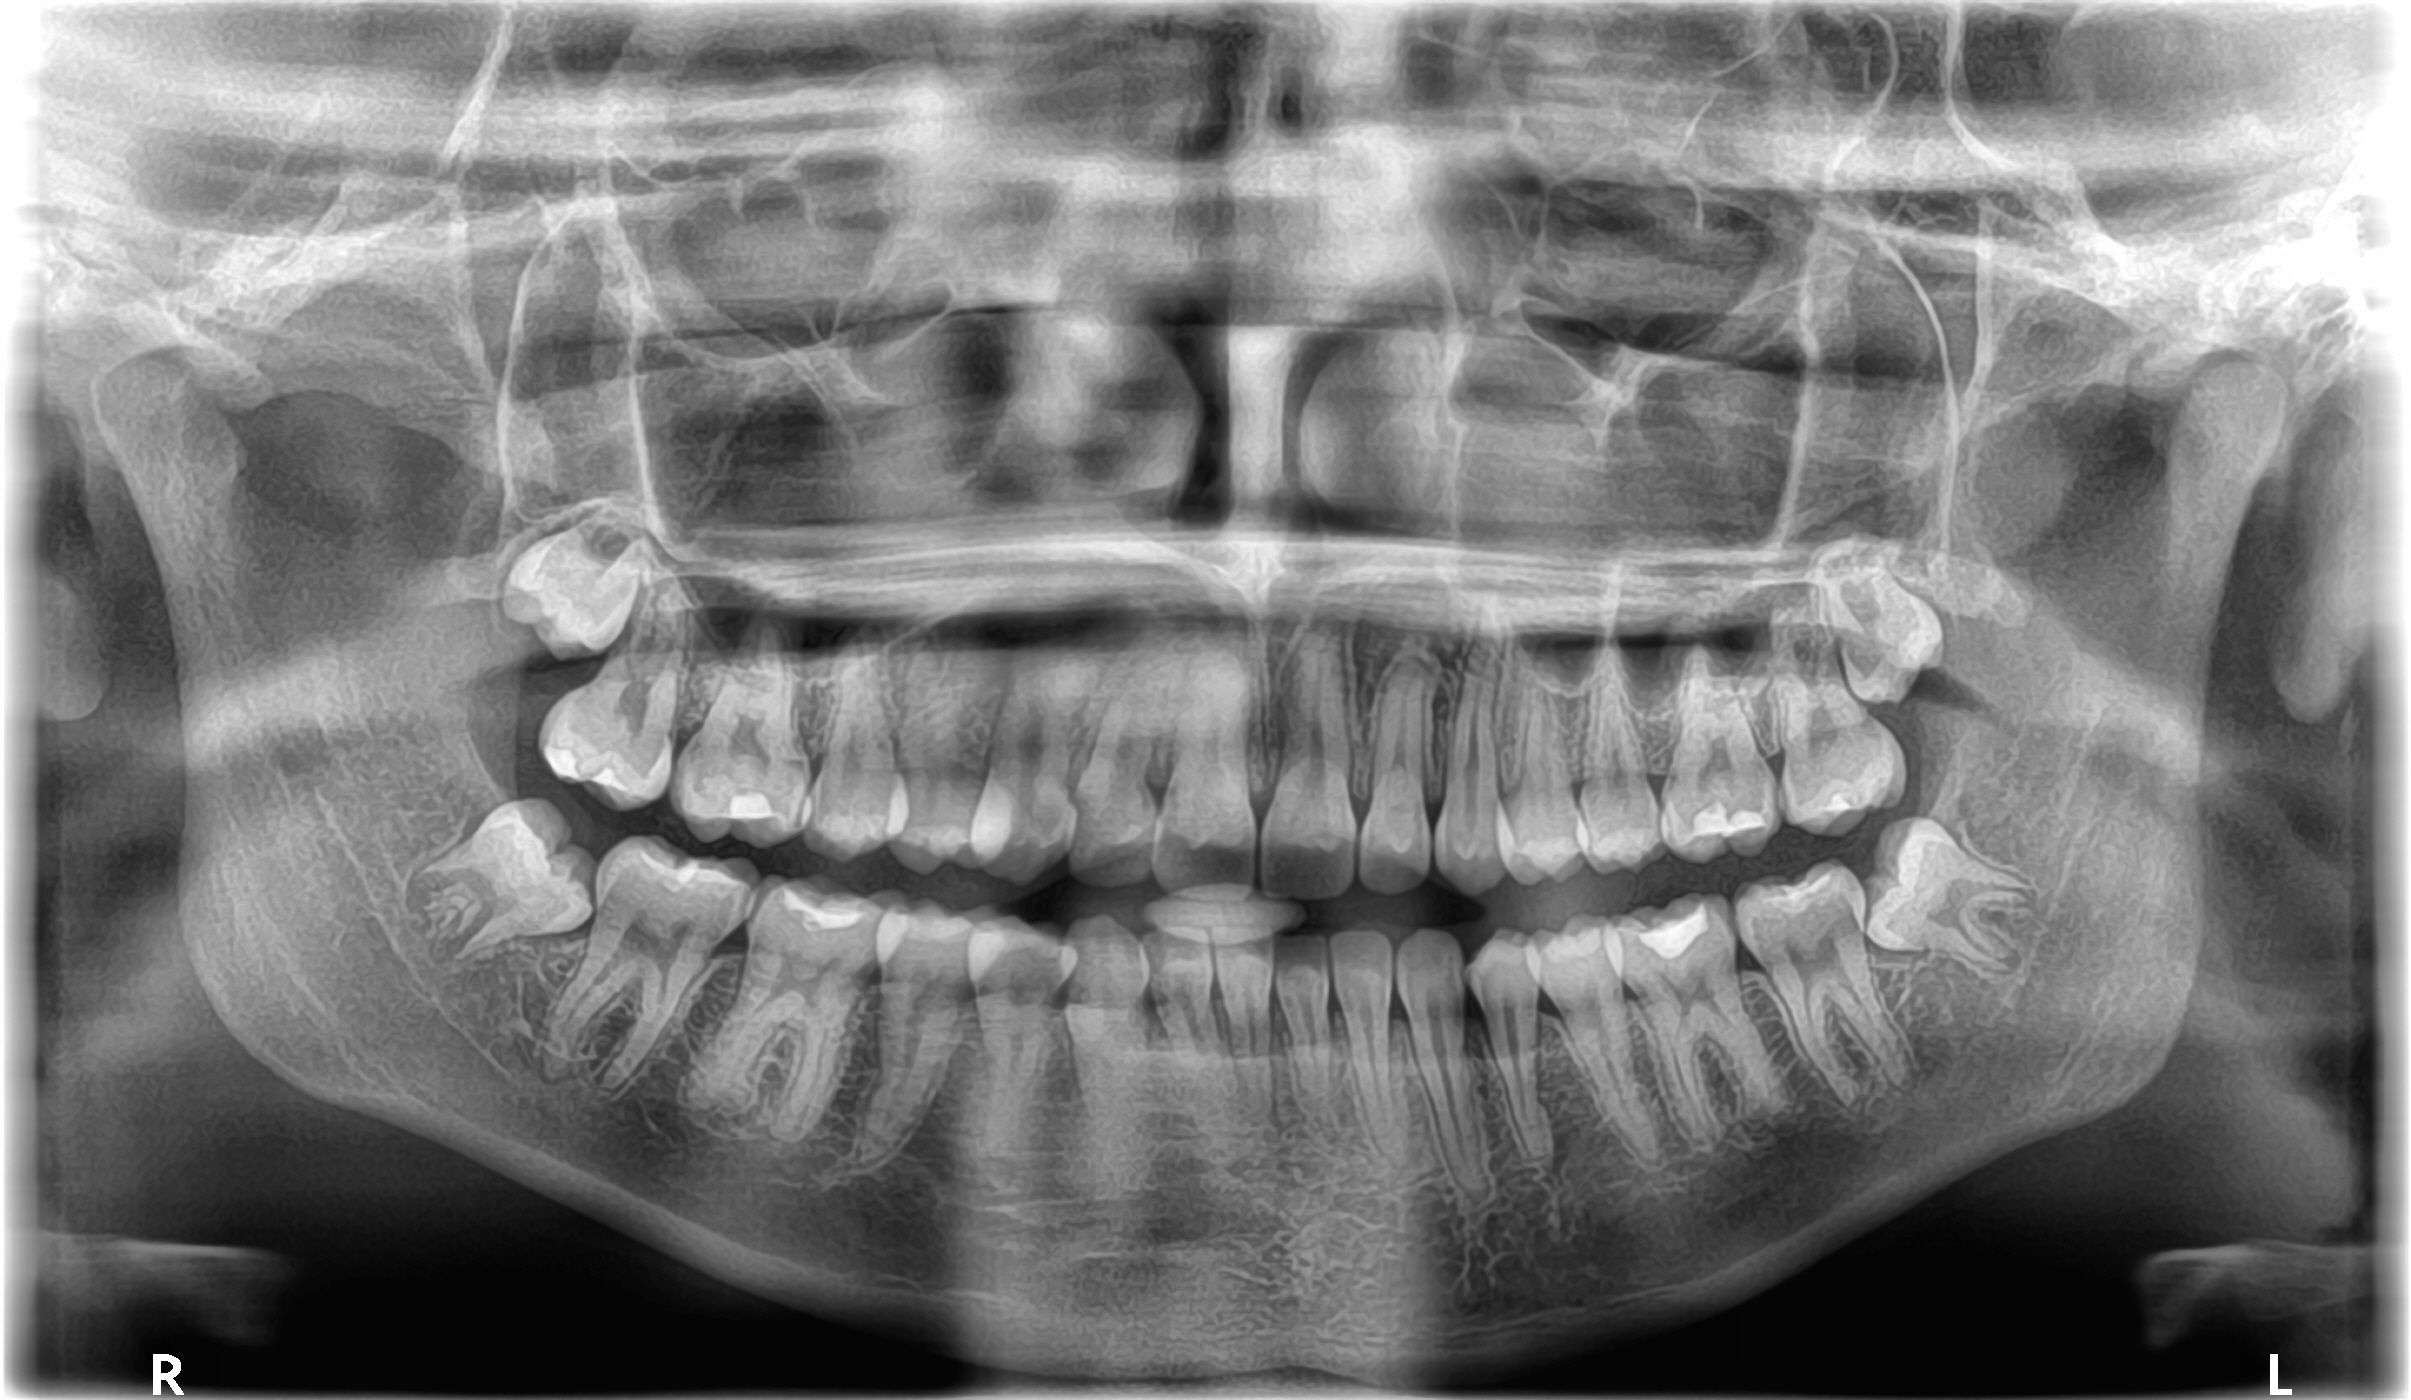

At Palmetto Oral & Maxillofacial Surgeons, P.A., our team performs comprehensive evaluations using advanced imaging to determine if extraction is necessary. Early assessment—often in the mid- to late-teen years—allows for a smoother procedure and easier recovery.